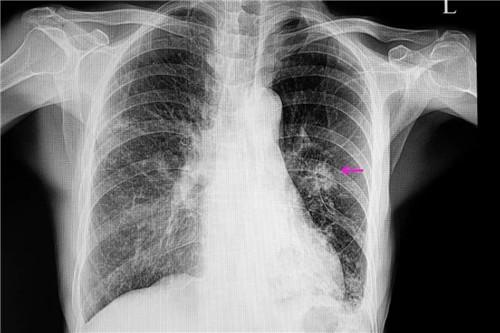

肺癌的影像学表现

肺癌的影像学表现,肺癌的ct影像学表现

中央型肺癌的3大影像学征象

【收藏】肺癌影像表现综述

肺癌的ct影像学表现

肺癌ct图片影像学

肺癌ct

肺癌ct图片